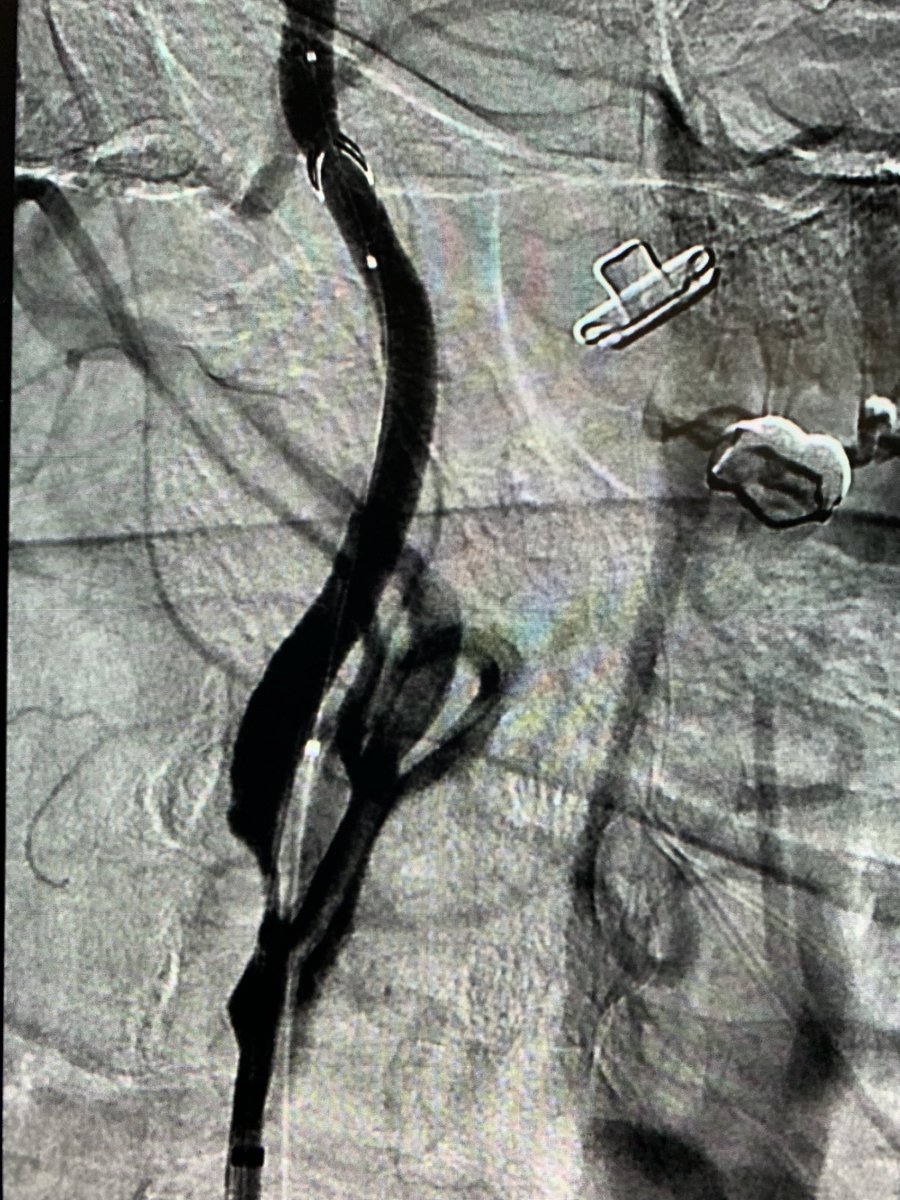

Before and after SFA atherectomy and angioplasty for CLI. #stopthechop @SIRspecialists @SIRRFS @MDAndersonNews @Interventional2